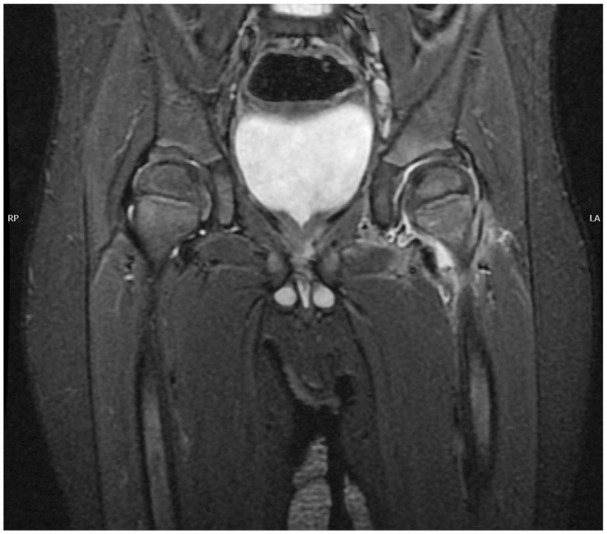

正确的诊断和治疗化脓性关节炎(SA)是必不可少的,以获得满意的结果,避免终身后果。诊断感染性关节炎并不总是那么容易,这就是为什么人们一直在寻找新的生物标志物。另一个诊断上的困难是由于金氏菌引起的脓毒性关节炎的增加,它与典型的金黄色葡萄球菌感染没有相同的体征和症状。磁共振成像在脓毒性关节炎的诊断中发挥着越来越重要的作用,许多研究都集中在这方面,特别是对相关病理的研究。已经发表了许多关于脓毒性关节炎的微创治疗的研究,尽管有证据表明应该谨慎对待结果。虽然大多数已发表的研究集中在髋关节和膝关节,但最近也有关于上肢、足部和踝关节SA的研究。最后,由于其病因不同且诊断难度较大,文献也关注了幼儿SA。

Correct diagnosis and treatment of septic arthritis (SA) are essential to achieve satisfactory results and avoid lifelong consequences. Diagnosing septic arthritis is not always easy, which is why new biomarkers have been sought. Another difficulty in diagnosis is the increase in septic arthritis due to Kingella Kingae, which does not show the same signs and symptoms as classic Staphylococcus aureus infections. Increasingly, magnetic resonance imaging plays a more fundamental role in diagnosing septic arthritis, and many studies are focused on this line, especially for the study of associated pathologies. Numerous studies have been published on less invasive treatments for septic arthritis, although the evidence suggests that the results should be taken cautiously. Although most of the published studies focus on the hip and knee, there have also been recent publications on SA in the upper limb, foot, and ankle. Finally, the literature also pays attention to SA in young children due to its different etiology and the greater difficulties in its diagnosis.